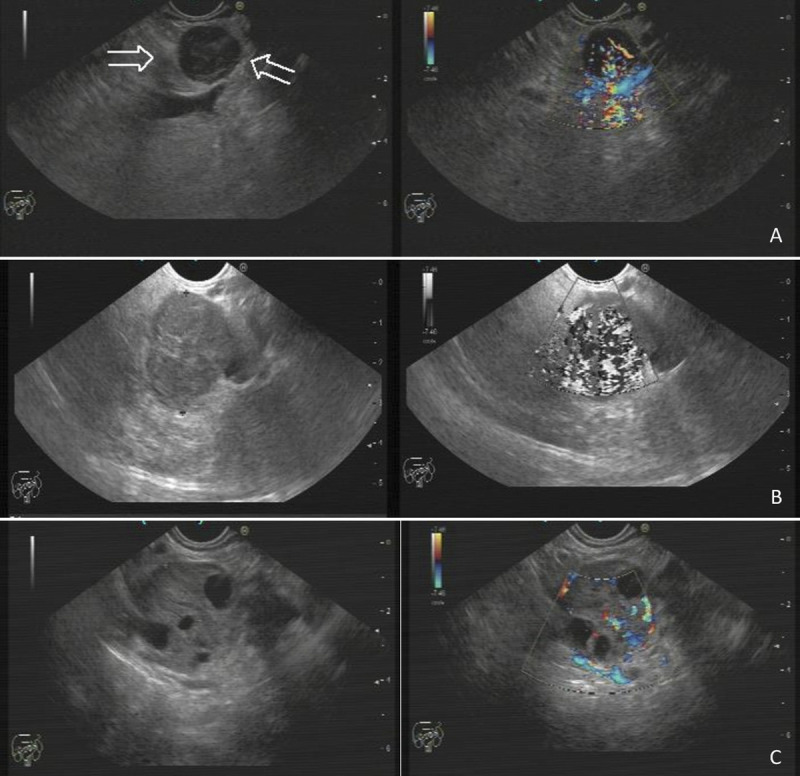

Methods: A total of 803 EUS images were collected from 44 patients who had a cyto/histo-pathologically confirmed diagnosis with EUS fine-needle aspiration or biopsy (FNA/B). First, raw EUS images were prepared for processing by AI via DL algorithms, and convolutional neural networks were utilized to train the machine to predict the grades from EUS images. IBM SPSS 25.0 program was used for statistical analyses.

Results: Thirty of the 44 patients (68%) were female, with a median age of 61 (range, 16-80) years. pNETs were mostly located in the pancreatic head: 24 cases (55%). Location was the neck in 3 (7%), body in 10 (22%), and tail in 7 (16%) patients. According to EUS-FNA/B results, 27 patients were grade 1 (G1) (61%); 12, grade 2 (G2) (27%); and 5, grade 3 (G3) (12%). In reference to the performance of AI for predicting the pathological grade, sensitivity was 94.29%; specificity, 97.14%; and accuracy, 96.19%. When the patient groups were subanalyzed as G1, G2, and G3 by the AI model to predict the pathological grade, the accuracy was as follows: for G1, 93.15%; for G2, 91.61%; and for G3, 98.05%.

Conclusions: This pilot study suggests that pNET grade prediction can be reliably done on EUS images using AI-based technology.